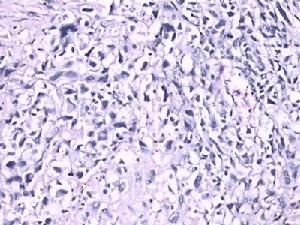

(1)增生期:病程的第1周腸壁上的淋巴結充血水腫,有大量巨噬細胞增生,淋巴細胞明顯腫脹,傷寒桿菌被單核細胞-巨細胞吞噬後大多仍在細胞內繼續繁殖,並隨淋巴-單核細胞散布至全身。在這一階段,傷寒桿菌和毒素不斷進入血液引起全身症狀。

(2)壞死期:病程的第2周。由於細菌毒素的作用以及巨噬細胞過度增生壓迫血管局部缺血,導致腫脹的腸壁淋巴組織發生小灶性壞死,並融合擴大成片狀